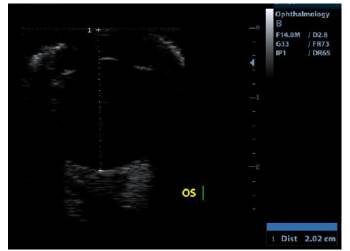

Se realizó ecografía ocular con transductor lineal de 14 MHz para evaluar extensión de la lesión, se apreció engrosamiento iridal severo en región ventrolateral del mismo con presencia de una masa adherida (no medida) con una porción hipoecoica hacia anterior y dos porciones anecoicas hacia posterior de la lesión (Figura 4), la ecogenicidad de la cámara anterior, cámara posterior y cámara vítrea se encontró conservada, la posición y ecogenicidad del lente se encontraron adecuadas, la túnica posterior estaba posicionada adecuadamente (Figura 5).

Figura 4 Aumento de volumen iridal (línea punteada) y presencia de quistes (marcadores) a la ecografía ocular (corte axial horizontal).